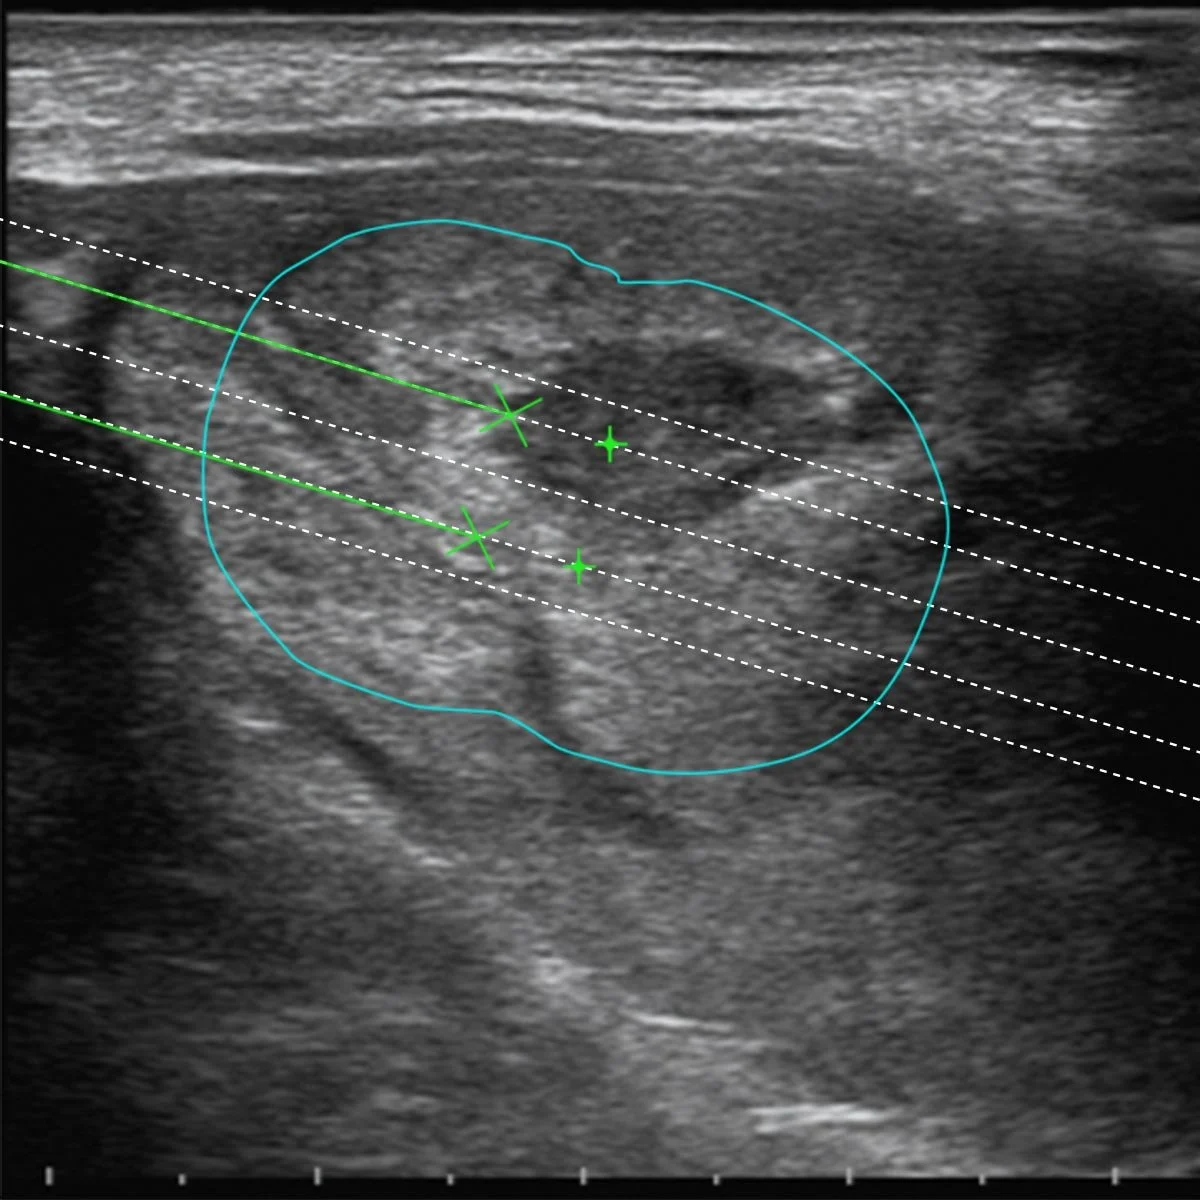

Guiding Systems and dedicated Biopsy Software

The Guiding Systems on the Esaote probes have been designed for each kind of application to help the operator when positioning several fibres inside the lesion to be treated. The dedicated Biopsy Software for EchoLaser Thermal Ablation inside the US unit displays the guidelines on the screen for each different guide in order to allow for an evaluation of the best positioning of the applicator in reference to the size, morphology and position of the lesion.